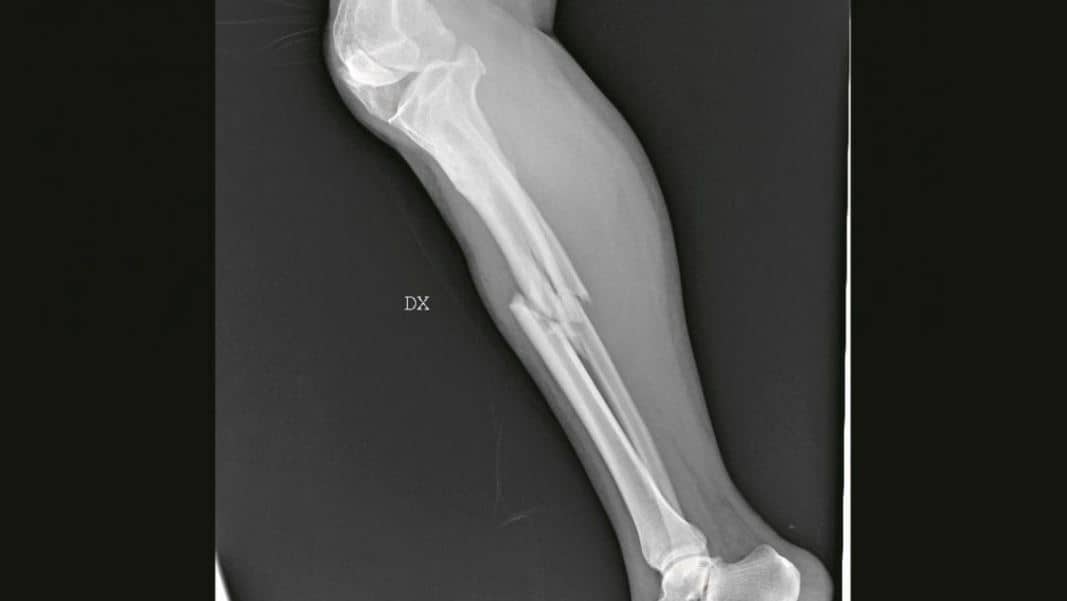

Una delle radiografie in mostra Credit: San Carlo di Milano

Da pugnali conficcati nell'addome a ossa rotte: la violenza sulle donne appare senza filtri nelle radiografie in mostra a Milano

La forza delle immagini contro la violenza sulle donne: una raccolta di foto e radiografie anonime raffigurano la parte più profonda delle vittime di violenza, quella che è stata ferita. Sono le immagini esposte nel rispetto dell’anonimato per scuotere le coscienze sul fenomeno in una mostra che verrà allestita nell’ospedale San Carlo di Milano, da giovedì 21 novembre a domenica 8 dicembre.

L’ideatrice della mostra di sensibilizzazione è la chirurga Maria Grazie Vantadori: “Le donne, spesso, non hanno la forza di raccontare. Ma i corpi e le lesioni parlano per loro, rivelano vertigini di orrore quotidiano. Per questo ho deciso di mostrare la violenza domestica come la vediamo noi al pronto soccorso: ossa rotte, nasi spaccati, occhi pesti, mani fratturate, polsi slogati, gambe rotte, coltellate, bruciature, morsi, segni di strangolamento, ferite da torture con pezzi di vetro. O addirittura un pugnale nella schiena. Lo scenario di una guerra nascosta nelle mura di casa che i numeri non riescono a raccontare”.